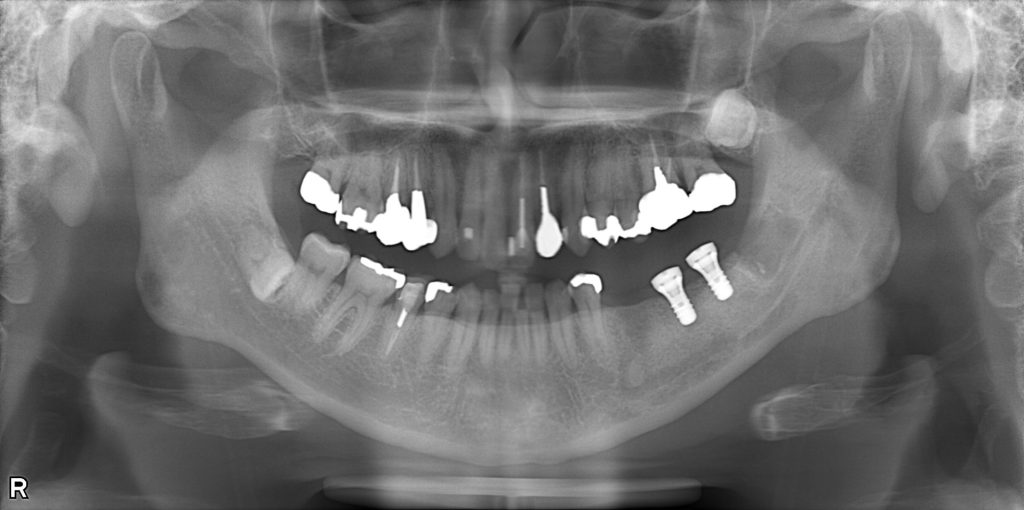

レントゲン画像(抜歯前)

レントゲン画像(インプラント埋入後)

左下7(第二大臼歯)は、歯根破折により数年前に他院で抜歯済み。

左下6(第一大臼歯)は、過去に近心根の歯根破折に対して

歯根分割抜歯(ヘミセクション)が行われており、遠心根のみ残存している状態。

欠損部位は、左下5(第二小臼歯)および左

下6遠心根を支台歯としたブリッジ補綴により修復されていた。

左下5・左下6遠心根ともに、歯質量・歯周組織の状態から、

長期的予後としては良好とは言えない状態であることを説明。

また、左下6遠心根についても構造的・機能的予後が不良と判断。